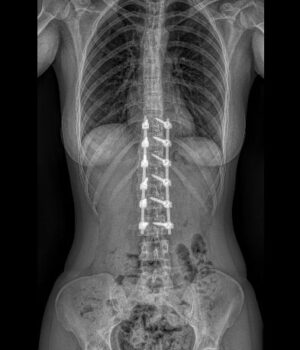

RTG celé páteře (EOS)

Jako první zobrazovací metodu obvykle provádíme RTG, případně EOS. Poskytuje nám obraz páteře v předozadní a boční rovině a umožňuje měřit stupeň zakřivení. RTG provádíme pravidelně na každé kontrole k posouzení vývoje křivky.